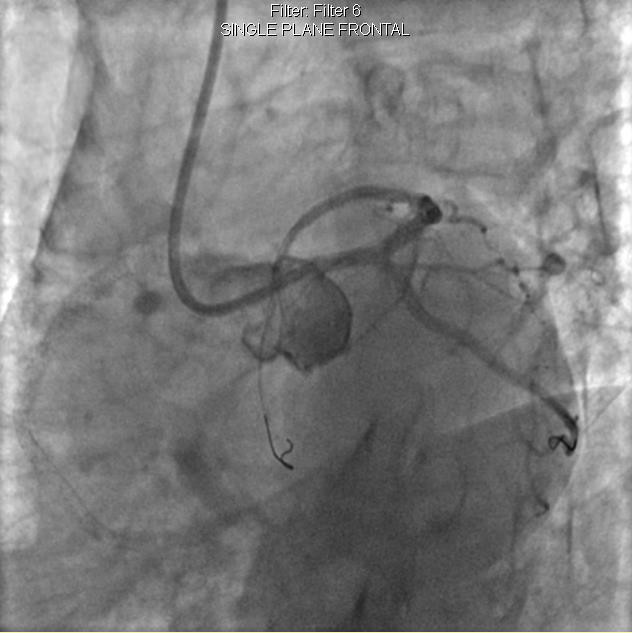

李先生足位術前影像

李先生足位術后影像

手術方案確定之后,在心血管內三科趙景新主任、介入醫學科富孝晨主任的配合下,翟光耀主任親自擔任主刀,分別依次對李先生的三支動脈進行了完全血運重建。由于手術進展順利,李先生術中沒有任何癥狀,耐受良好,于是成功的將三支動脈“一站式”治療!術中,由于李先生左主干遠端分叉處存在嚴重病變,翟光耀主任選擇國際指南推薦的DK-mini-Crush技術,確保了分叉處兩支主干開口均萬無一失。據悉,DK-mini-Crush技術是目前冠脈分叉病變領域最為復雜及難以掌握的介入技術之一,對手術醫生經驗、體力均提出了極大的挑戰。極為擅長復雜介入技術的翟光耀主任卻用嫻熟的技術確保了李先生手術的成功。

冠狀動脈嚴重鈣化合并狹窄病變是冠脈介入的一大難題,血運重建難度大,成功率低,并發癥發生率高,該例患者的成功救治標志著我院冠脈介入水平又躍上了一個新的臺階。